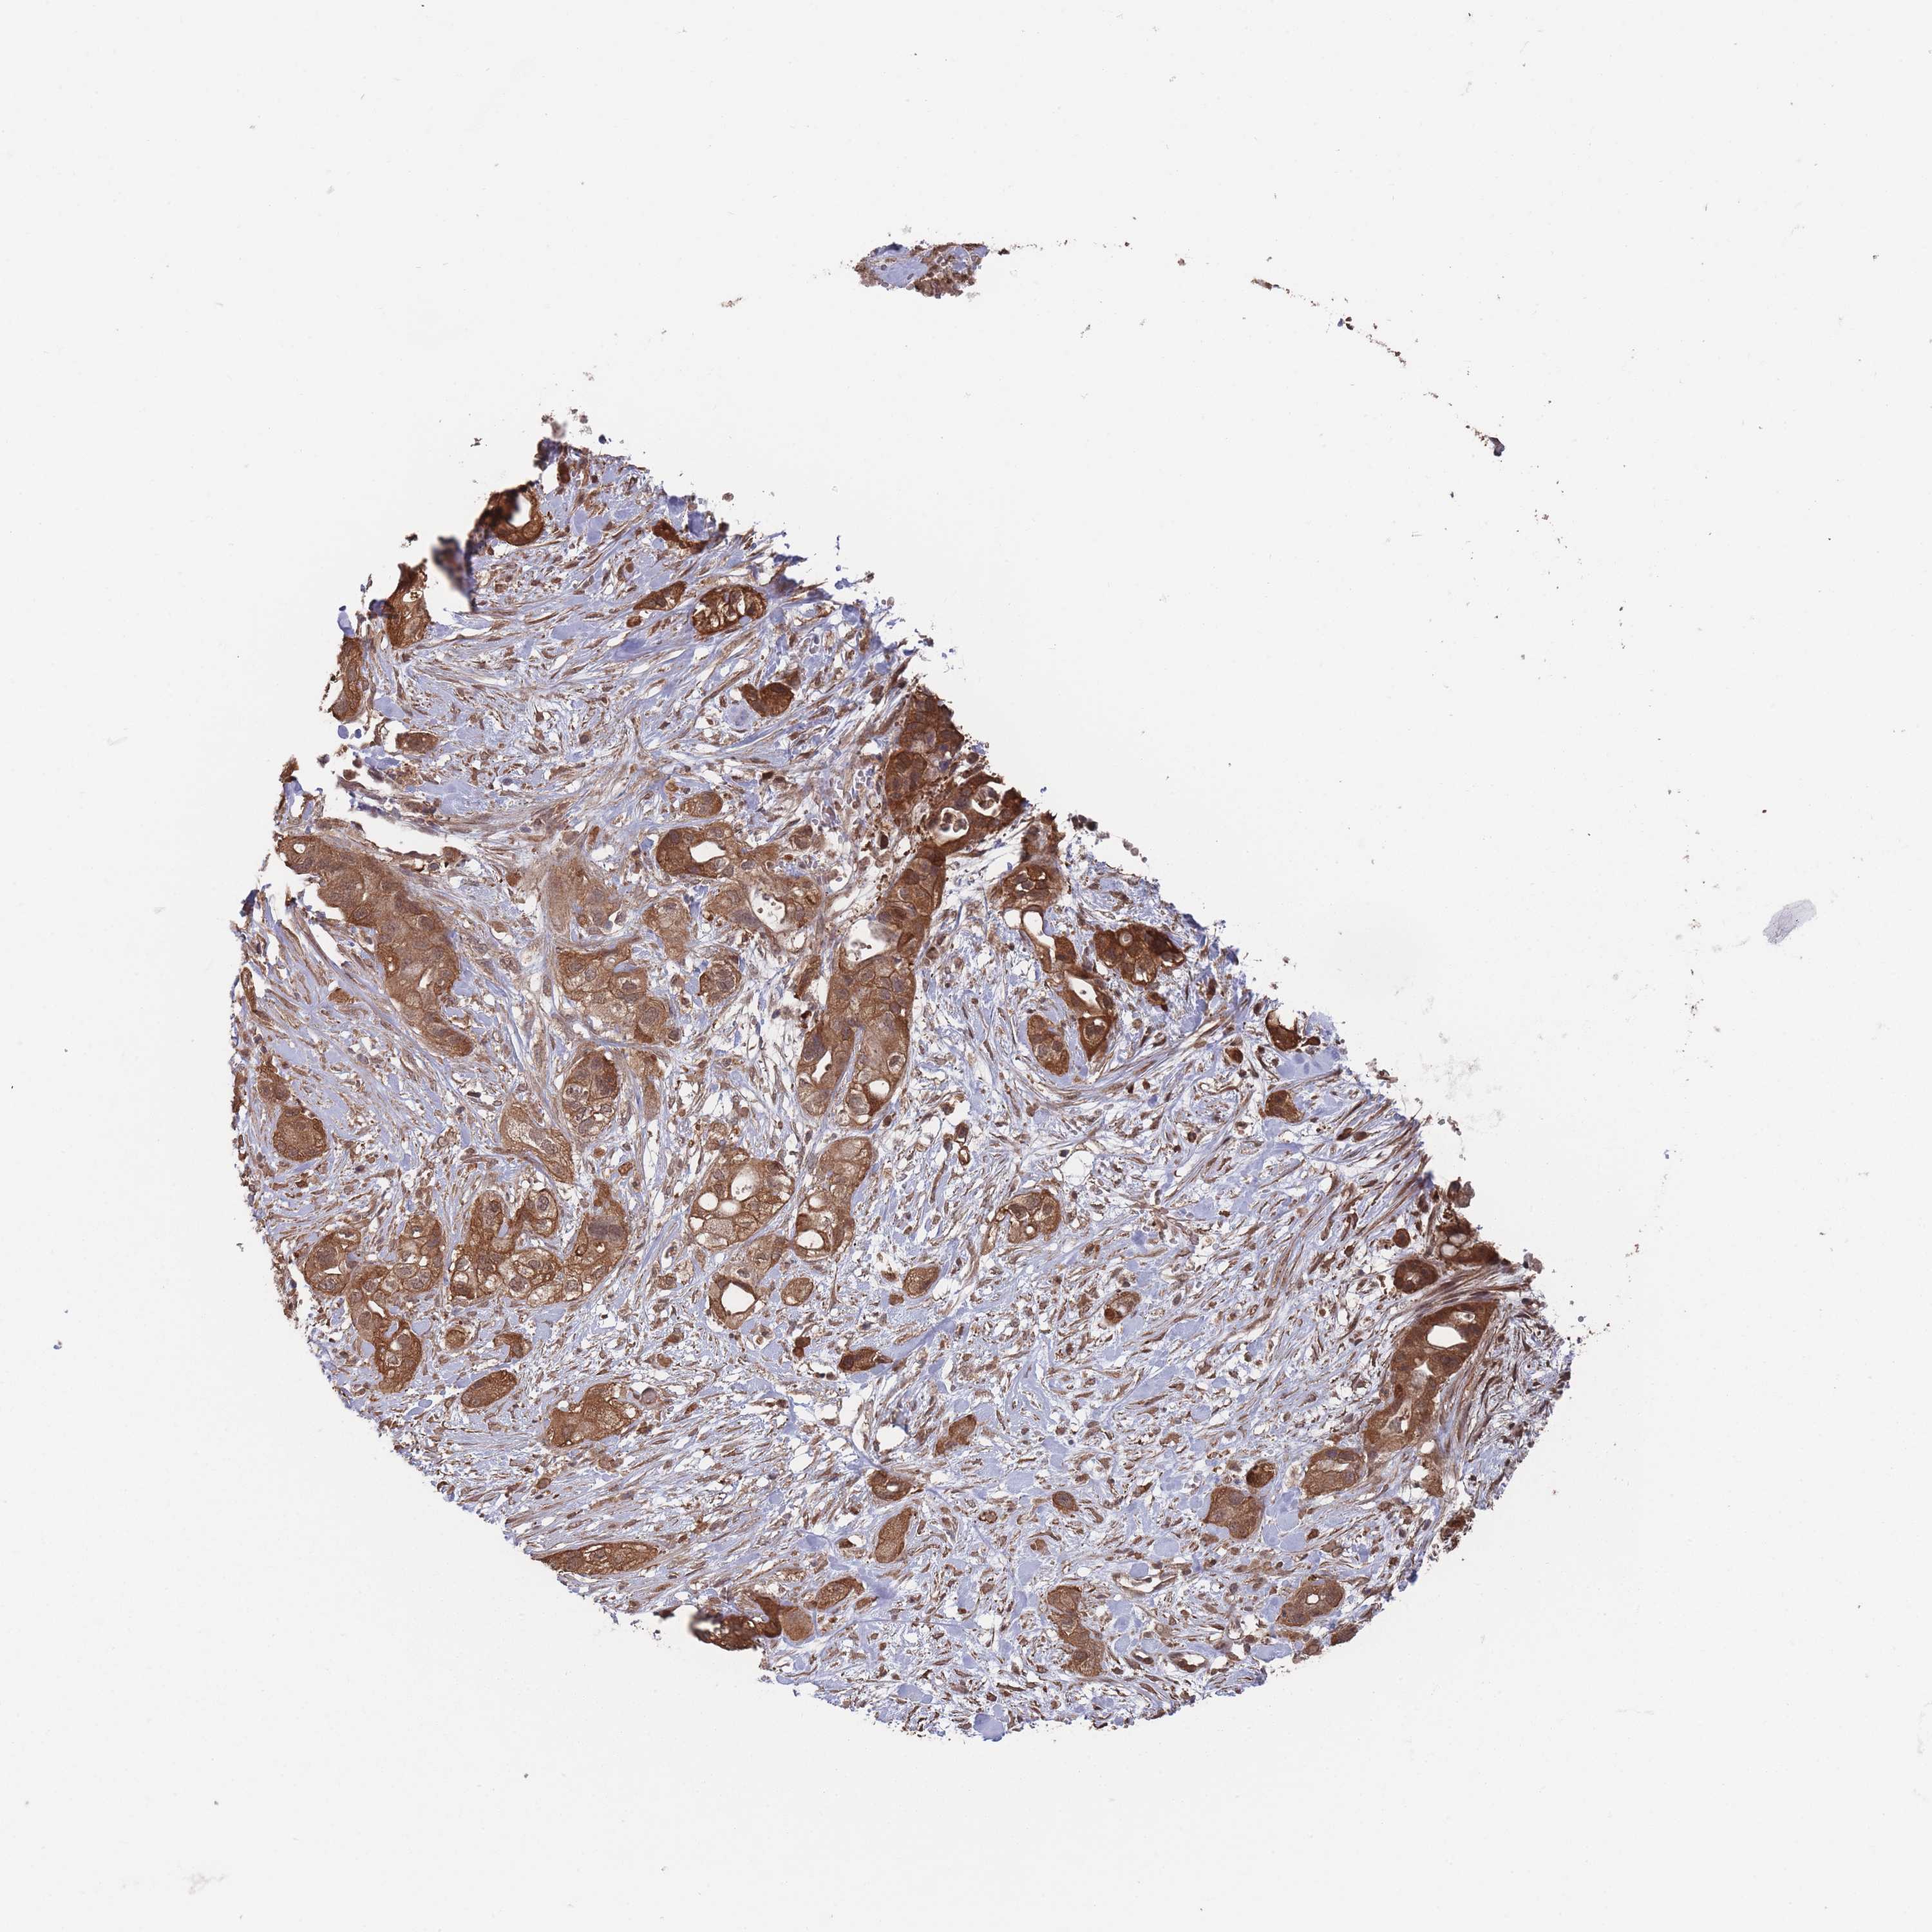

PANCREATIC CANCER - Protein expressioni

A mouse-over function shows sample information and annotation data. Click on an image to view it in a full screen mode. Samples can be filtered based on level of antibody staining by selecting one or several of the following categories: high, medium, low and not detected. The assay and annotation is described here.

Note that samples used for immunohistochemistry by the Human Protein Atlas do not correspond to samples in the TCGA dataset.

Antibody stainingi

Antibody staining in the annotated cell types in the current human tissue is reported as not detected, low, medium, or high, based on conventional immunohistochemistry profiling in selected tissues. This score is based on the combination of the staining intensity and fraction of stained cells.

Each image is clickable and will lead to virtual microscopy that enables deeper exploration of all samples and also displays staining intensity scores, fraction scores and subcellular localization as well as patient and tissue information for each sample.

Antibody HPA050275

Staining

High

Medium

Low

Not detected

Intensity

Strong

Moderate

Weak

Negative

Quantity

>75%

75%-25%

<25%

None

Location

Nuclear

Cytoplasmic/membranous

Cytoplasmic/membranous,nuclear

Adenocarcinoma, NOS